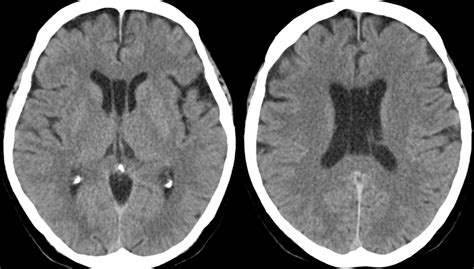

Now, let’s get more specific about the location of the cavum septum pellucidum . As mentioned, it’s found in the anterior (front) part of the brain. To be even more precise, it’s situated within the septum pellucidum, which is a thin sheet of gray matter that divides the two cerebral hemispheres. Imagine looking at a brain from the side, right in the middle. The CSP lies just behind the genu (the front bend) of the corpus callosum and in front of the fornix, another important brain structure. It’s essentially sandwiched between these two major white matter tracts. The observation of the CSP is typically made during neuroimaging studies, such as Magnetic Resonance Imaging (MRI) or Computed Tomography (CT) scans, and sometimes even during ultrasound examinations, especially in fetuses. When a radiologist or neurologist looks at these scans, they are examining slices of the brain. The CSP will appear as a distinct, often cerebrospinal fluid (CSF)-filled space within the midline structures. The anterior position is significant because it’s in a region of the brain that plays a crucial role in higher cognitive functions, emotions, and decision-making. While the CSP itself doesn’t directly perform these functions, its presence in this critical area has led to investigations into potential associations. It’s important to reiterate that the cavum septum pellucidum is observed anterior to many key structures involved in communication between brain hemispheres and in relaying sensory information. For example, it lies anterior to the columns of the fornix and posterior to the anterior commissure. Its location is consistently midline, making it a landmark for surgeons and radiologists when assessing brain anatomy. The size and shape of the CSP can vary considerably. Some are tiny slits, barely detectable, while others can be more pronounced. The measurement of the CSP is often done in millimeters. A CSP is generally considered to be of significant size if it measures more than 5 mm in width or if it extends posteriorly beyond the anterior margin of the fornix. This is where clinical correlation becomes important. While a small CSP is usually benign, a larger or more extensively developed CSP might be associated with certain neurodevelopmental disorders. For instance, it has been observed more frequently in individuals with conditions like schizophrenia, bipolar disorder, attention-deficit/hyperactivity disorder (ADHD), and certain congenital malformations. However, it’s crucial to understand that association does not equal causation . Many people with a significant CSP do not have any of these conditions, and many people with these conditions do not have a CSP. The observation of a CSP is just one piece of a much larger puzzle in understanding brain development and function. It’s a visual marker that prompts further consideration and investigation in specific clinical contexts. So, when you hear that the CSP is observed anterior to certain structures, it’s essentially pinpointing its precise anatomical address within the intricate map of the human brain.